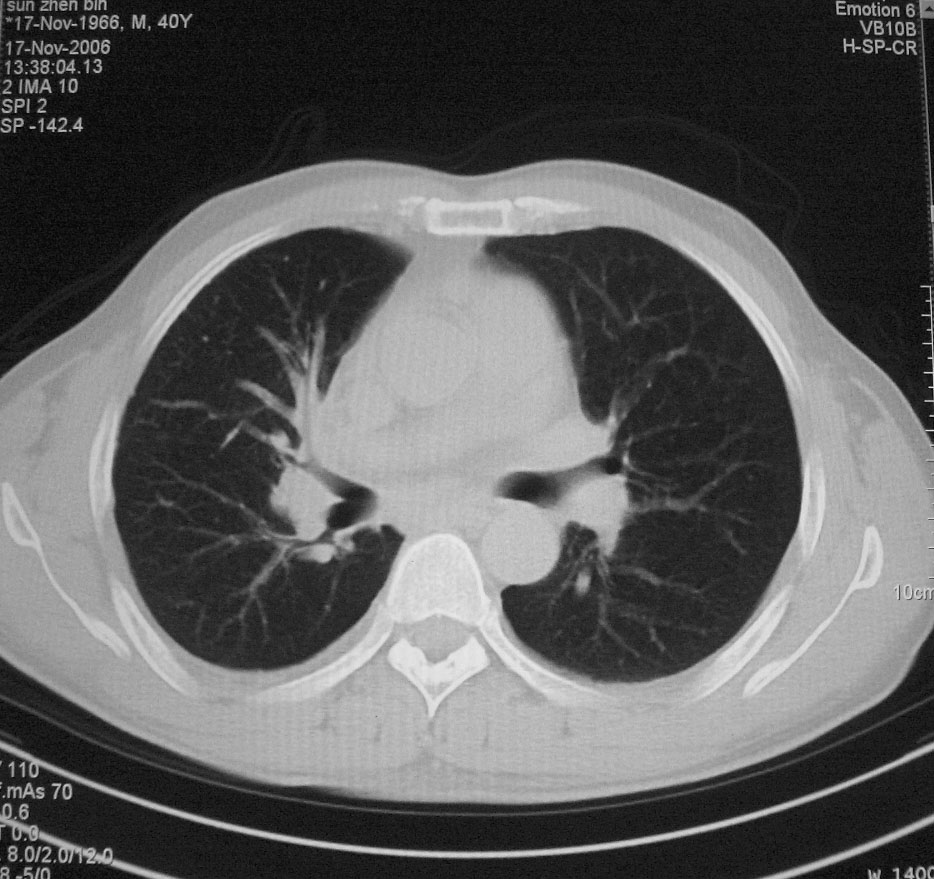

标题: CT5485:[原创]肺部占位请讨论

右上肺ca并肺不张,纵隔淋巴结转移

右肺上叶中央型肺癌并上叶肺不张、纵隔淋巴结肿大

右上叶支气管后壁明显增厚,支持右肺上叶中央型肺癌伴右上叶肺不张、纵隔淋巴结肿大。

右上叶支气管后壁明显增厚,支持右肺上叶中央型肺癌伴右上叶肺不张、纵隔淋巴结肿大。建议支气管镜检查。

右上肺中央性肺癌伴右侧胸腔少量积液!右上肺胸膜下还有一小病灶,不完全排除结核,但个人支持恶性肿瘤!建议早穿刺活检。

右上叶支气管开口变窄,纵隔见肿大的淋巴结。支持右上叶中心型肺癌并右上叶不张纵隔淋巴结肿大。

右肺上叶中央型肺癌并上叶肺不张、纵隔淋巴结肿大.右侧少量胸腔积液。

右肺上叶支气管后壁增厚,呈鼠尾状狭窄,纵隔内未见明显增大的淋巴结影,考虑为中央型肺癌伴右上肺不张